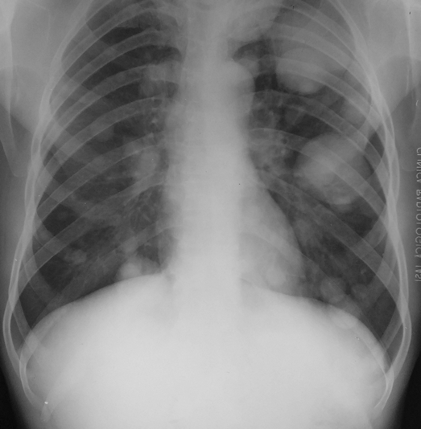

Rx toracică, incidență P-A

DESCRIERE:

pe tot teritoriul pulmonar, bilateral → opacități nodulare multiple de dimensiuni variabile, intensitate medie-mare, omogene, cu contur net

distribuție anarhică

blocuri adenopatice la niv. hilurilor pulmonare

DX: MTS pulmonare hematogene

DD:

hidatidoză - dimensiuni mai mari

bronhopneumonie - contur neregulat, neomogene, distribuție bazală